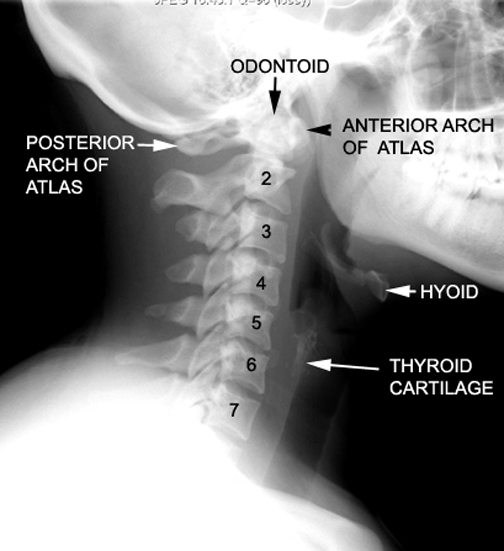

Identify the Odontoid and posterior arch of Atlas. Click the image for labeling.